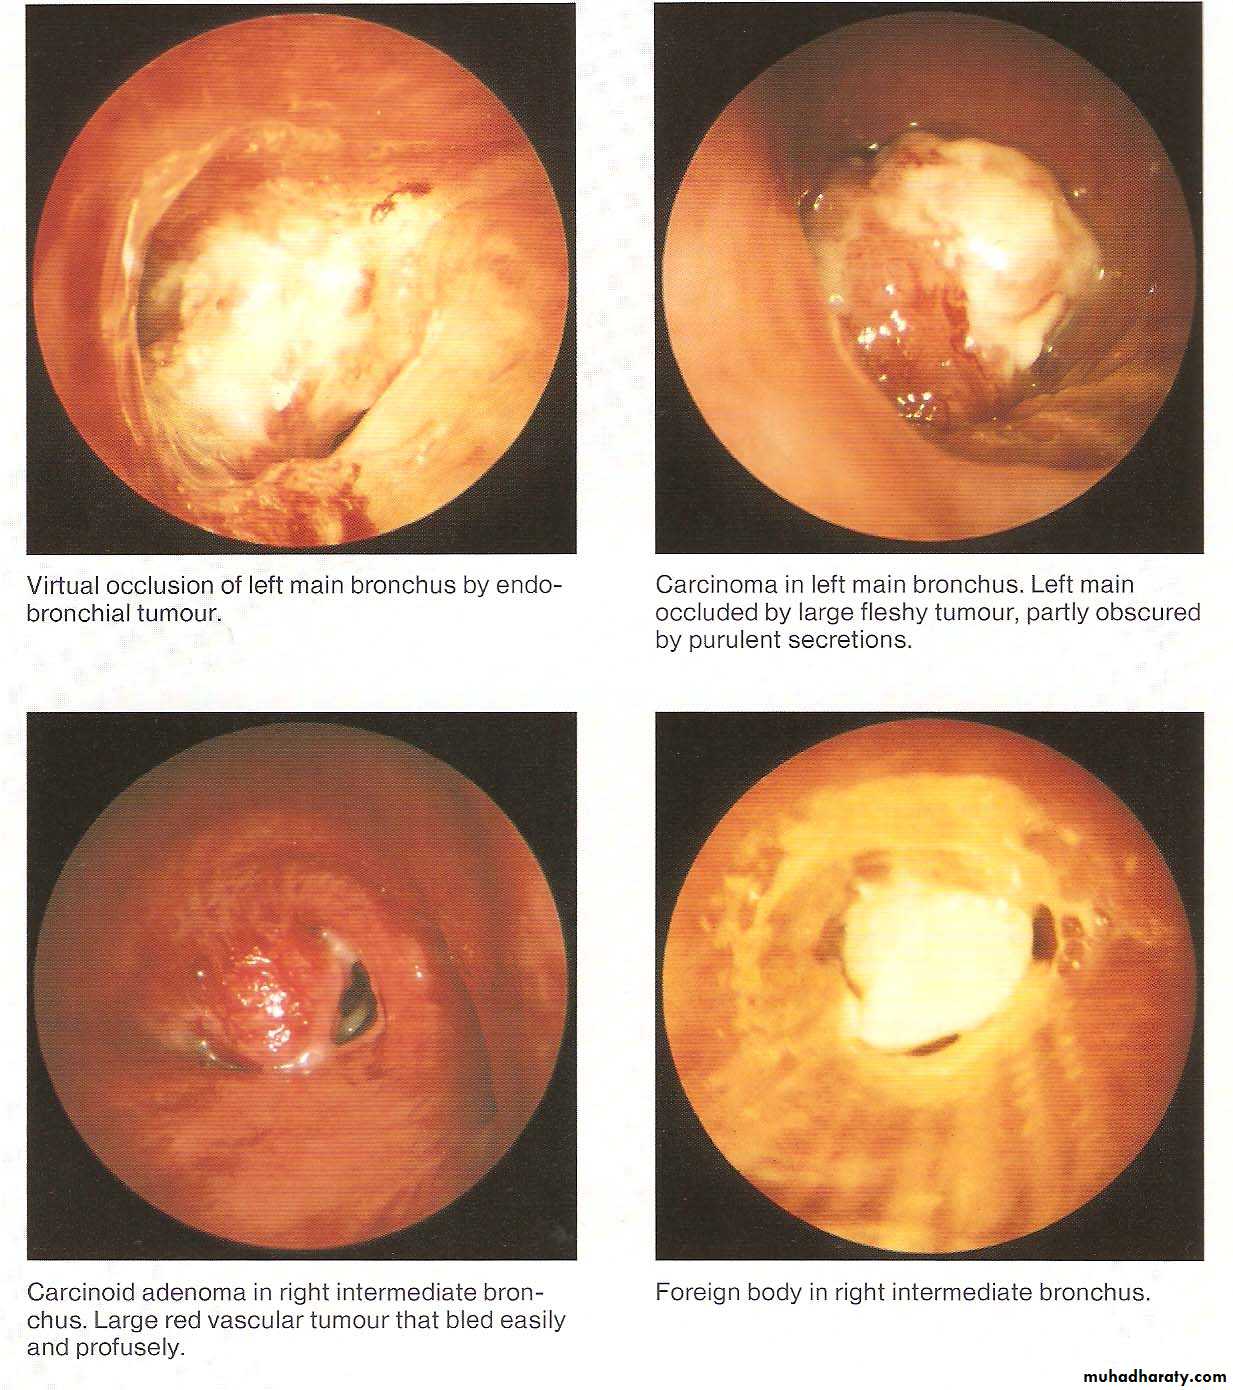

• Normal Bronchoscopic Findings

• Abnormal Bronchoscopic Findings

Diagnostic indications include tissue diagnosis, detection and staging of lung malignancy, evaluation of diffuse lung diseases like sarcoidosis and idiopathic interstitial pneumonias, pulmonary inspection of burn patients, identification of organisms infecting the respiratory tract and lungs.

As a therapeutic modality, bronchoscopy is used to place stents to protect airways vulnerable to collapse or occlusion, to remove foreign bodies or masses, to treat early stage endobronchial malignancy.